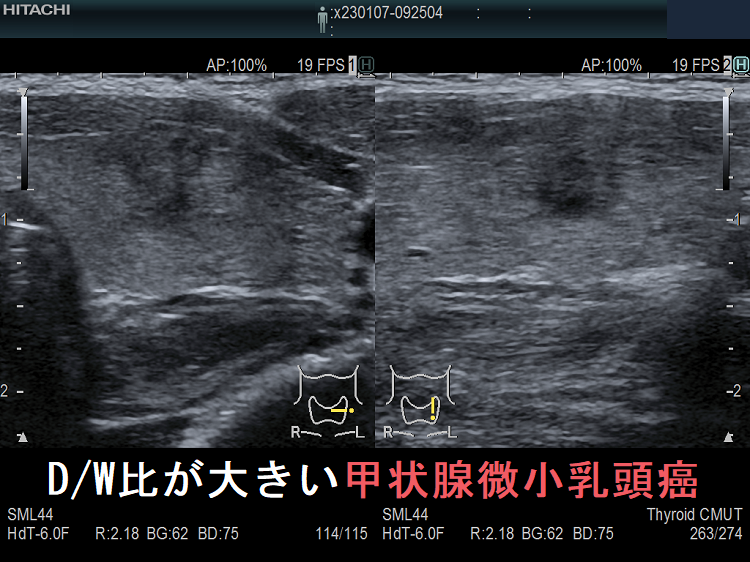

- D/W比が大きい甲状腺微小乳頭癌 超音波(エコー)画像